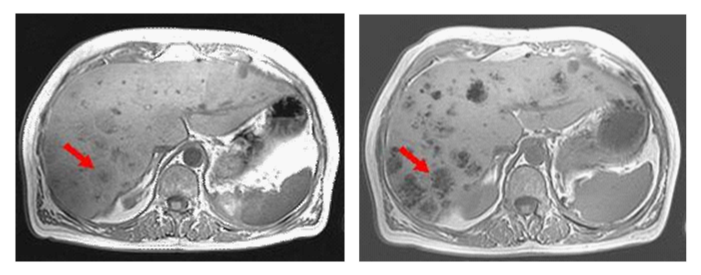

The MRI of the liver was performed in a 3 Tesla high-field magnet (TIM TRIO, SIEMENS) with standard examination protocol in T1-weighted and T2-weighted images with a liver-specific contrast agent (Primovist®, from Bayer Healthcare) and showed a surprising signal change in individual metastases already in the native Gradient Echo T1-weighted images (FL 2D, TR 450ms/TE 9 and 11ms/flip 60°). Low signal differences at low different echo time are negligible. Figure 1a and b before the start of therapy multiple liver metastases of the renal cell carcinoma with a donut phenomenon can be detected. In the follow-up metastases show only a partial reduction under Inlyta® therapy, but a hypointense and central, punctiform-confluent signal reduction (arrow).

Figure 1 MRI, TIM Trio, 3 Tesla (Siemens), Gradient Echo T1-weighted transversal, native, before (a) and 6 months after initiation of therapy (b).